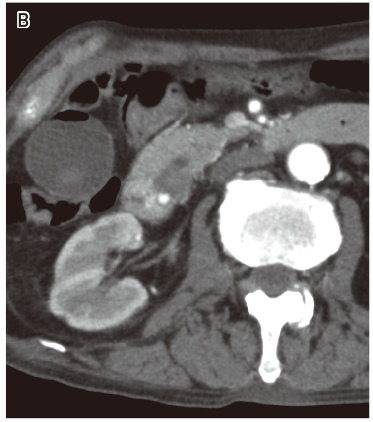

意識障害と発熱の精査加療目的に入院.低血糖(6 mg/dL)の補正により意識障害はすみやかに改善した.CTおよび超音波内視鏡検査にて総胆管結石による胆石性胆管炎が発熱の原因と考えられ,内視鏡的採石術および内視鏡的乳頭括約筋切開術(endoscopic sphincterotomy:EST)を施行された.入院6日目に血便と貧血の進行および血圧低下があり原因検索目的に造影CTを施行した.

図1 B)造影CT動脈相

図1 C)造影CT平衡相